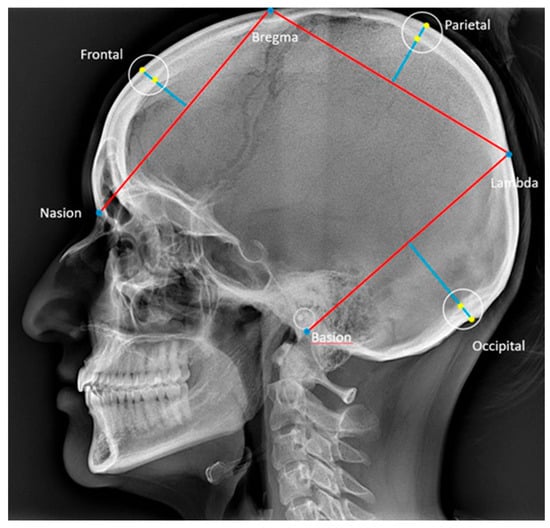

The cephalometric analysis was carried out according to Björk [27], and reference points and lines are described in Table 1 and illustrated in Figure 2.

Figure 2.

Reference points and lines used for the description of the craniofacial morphology [27]. ML: mandibular line, the tangent to the lower border of the mandible through gn. MBL: mandibular baseline, the line through pgn and ar. NL: nasal line, the line through sp and pm. NSL: nasion–sella line, the line through n and s. RL: ramus line, the tangent to the posterior border of the mandible. Ba: basion, the most postero-inferior point on the clivus. Ar: the point of intersection of the dorsal contours of the articular process of the mandible and the temporal bone. Gn: gnathion, the most inferior point on the mandibular symphysis. N: nasion, the most anterior point of the frontonasal suture. Pg: pogonion, the most anterior point of the mandibular symphysis. Pm: pterygomaxillare, the intersection between the nasal floor and the posterior contour of the maxilla. S: sella, the centre of the sella turcica, the upper limit of the sella turcica is defined as the line joining the tuberculum and the dorsum sellae. Sm: supramentale, the most posterior point on the anterior contour of the lower alveolar arch. Sp: spinal point, the apex of the anterior nasal spine. Ss: subspinale, the most posterior point on the anterior contour of the upper alveolar arch. Rli: ramus line inferior, the tangent point on the posterior border of the mandibular ramus to a line through ar. Pgn: Prognathion, the point on the mandibular symphysis with the maximum length from the condylion.